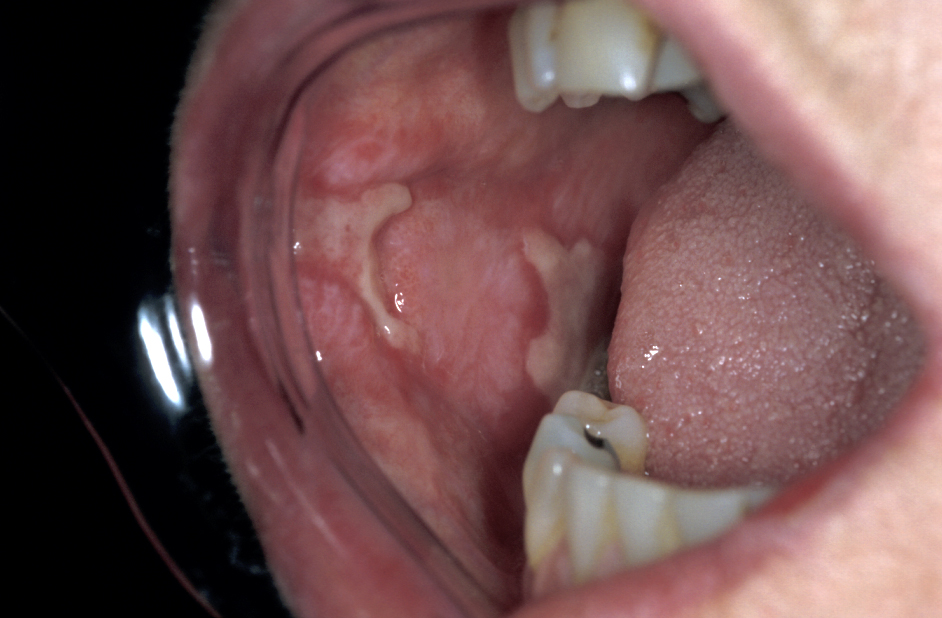

Lichen planus is a common skin condition (estimated 1 % of the world population), thought to be an immune disorder. It is an itchy non-infectious rash mostly affecting people older than 40 years, women are more often affected than men. Approximately in half of the cases not only the skin but also the oral mucosa is affected. Lichen planus may exclusively affect the oral mucosa.

Oral lichen planus typically exhibits white or reddish lace-like patterns on the surface of the tongue or inner cheek; if ulcers develop these may be painful. A biopsy may be necessary to confirm the diagnosis. A rare (approximately 1 %) sub-variant of oral lichen planus, erosive lichen planus (see Figure 4), is thought to belong to the group of potentially premalignant lesions whereas for the more common forms no such association is known. Oral lichen planus may persist for many months or years.